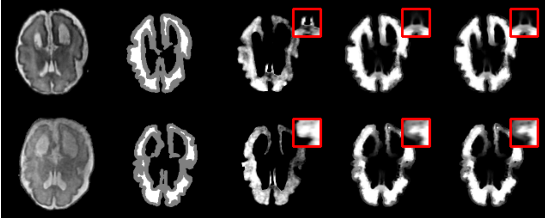

实验结果表 2表明,在仅提供Trimap的弱先验条件下,微搜索进化优化医学图像抠图算法在均方误差和梯度误差上,优于大多数对比方法。可视化结果(图 4)也显示,该方法能更准确地恢复前景与背景极其相似的模糊边缘区域。

图 4 有无微搜索策略的抠图预测结果可视化对比